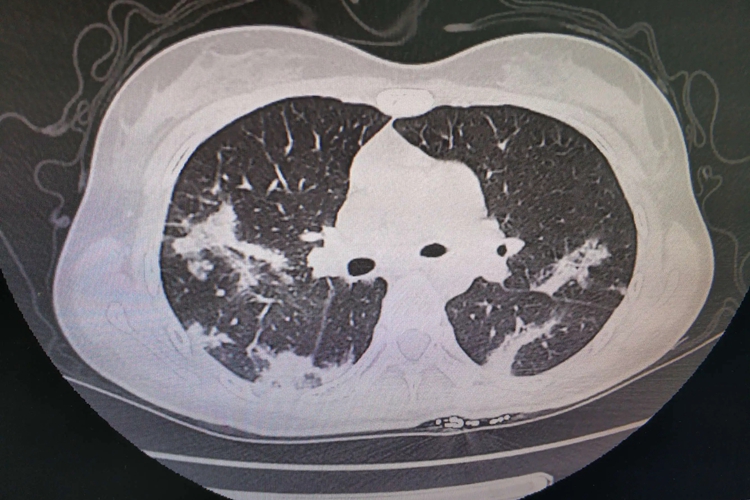

嗜酸性粒细胞肺炎即嗜酸性粒细胞性肺炎,CT检查可见肺部有磨玻璃影、实变影等。

嗜酸性粒细胞性肺炎的CT表现为肺内有磨玻璃影和实变影,可累及双肺,病灶主要分布在上肺和肺外周。CT检查结果可见肺部小叶间隔增厚,部分患者会有少量胸腔积液和纵隔淋巴结肿大,极少数的患者有空洞样病变。除此之外,患者多会出现呼吸困难、咳嗽、发热、盗汗,以及体重减轻和喘鸣等症状。